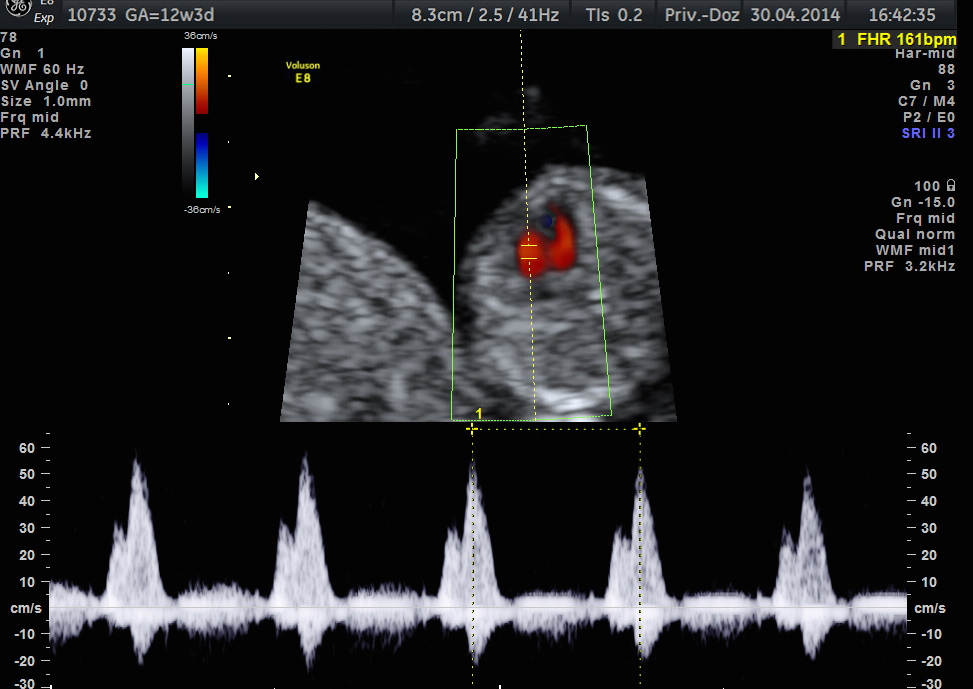

Darstellung des TK in der 13. SSW mittels Farb-Doppler

Normaler Blutfluss über die rechte Herzklappe (Trikuspitalklappe - TK) in der 13. Woche